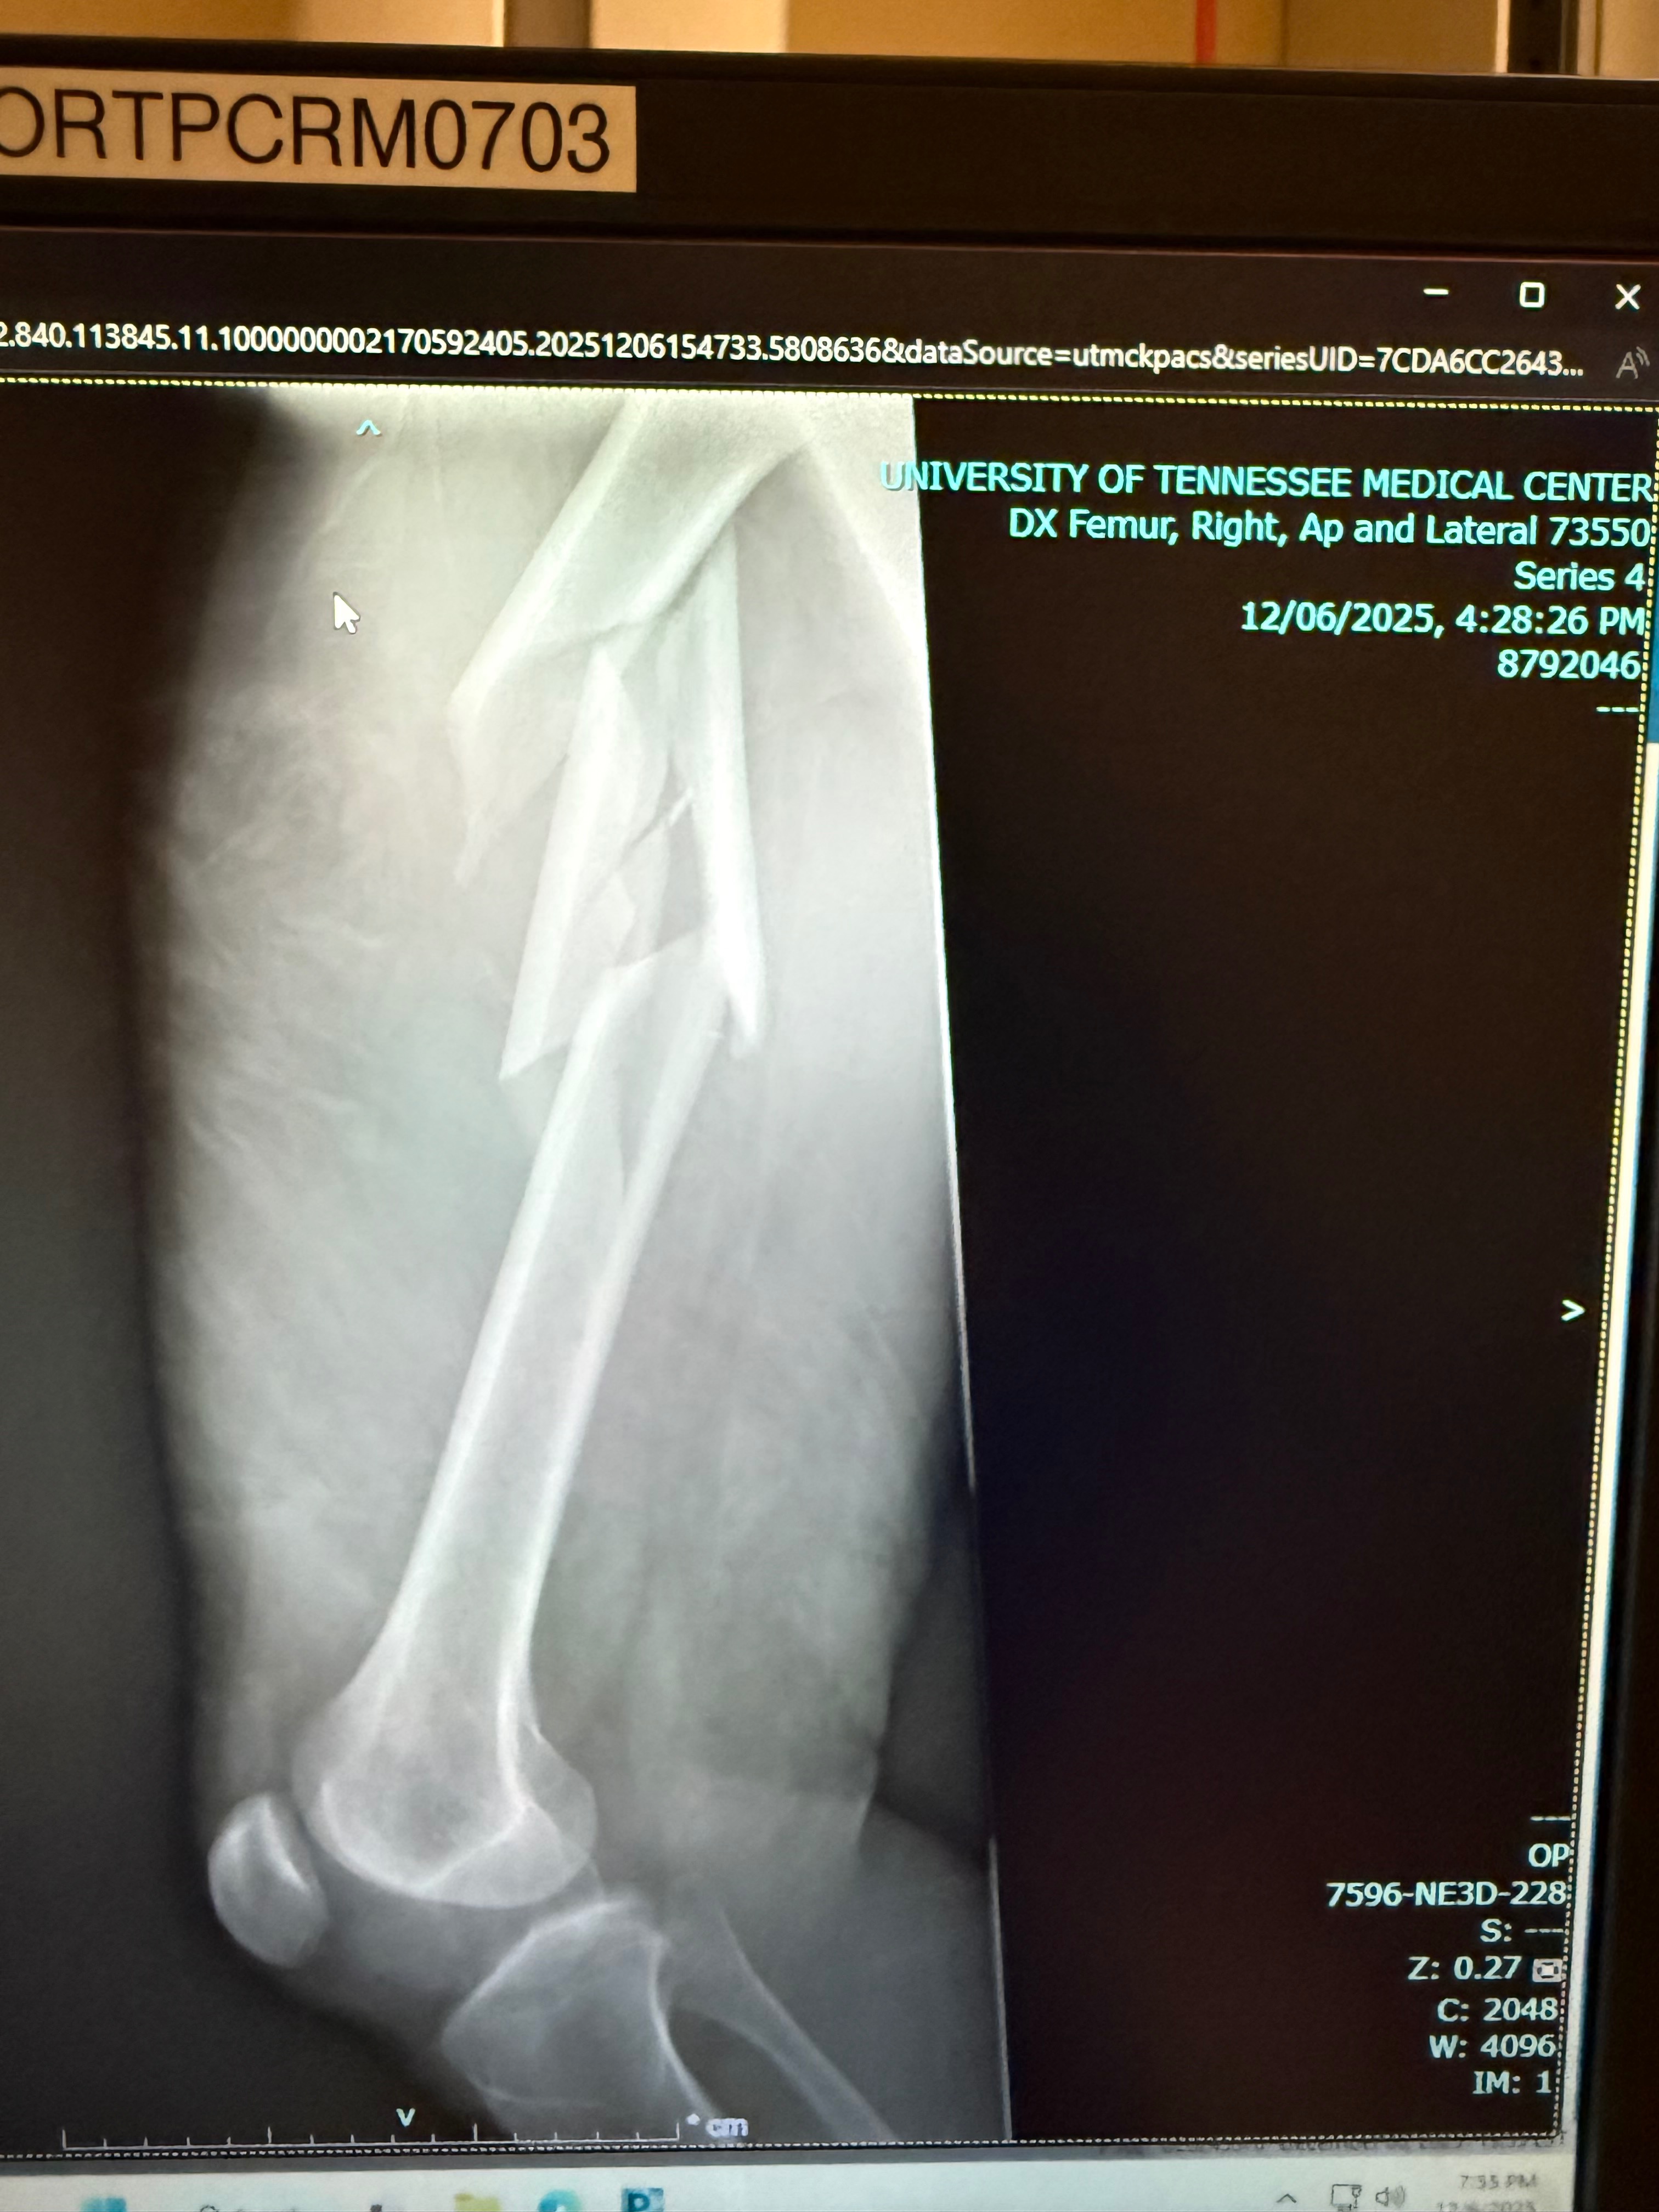

Este sábado 6 de diciembre, durante mi primer viaje de vacaciones, en Tennessee, esquiando, sufrí una caída que terminó en una fractura de fémur. En cuestión de minutos estaba siendo trasladado en helicóptero al hospital. Son de esos momentos que nunca imaginas que te van a suceder a ti.

Ya tuve la primera cirugía, pero surgieron complicaciones y ahora me esperan dos cirugías más para poder recuperar la movilidad y evitar secuelas permanentes.